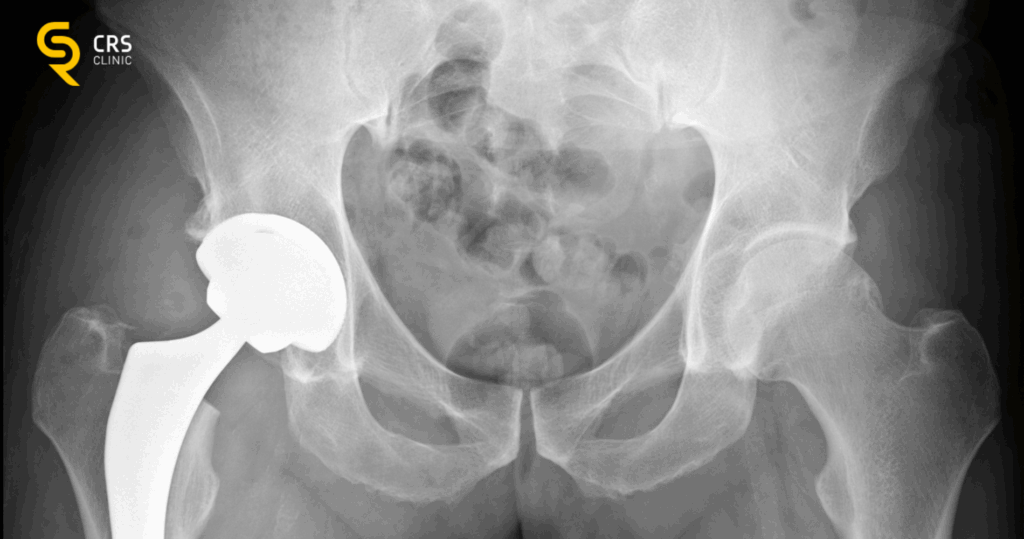

Leczenie operacyjne stawu biodrowego jest skuteczne, ale powinno być traktowane jako ostateczność. Jeśli leczenie zachowawcze nie przynosi efektów, a pacjent odczuwa silny ból nawet w spoczynku, można rozważyć endoprotezoplastykę, czyli wymianę stawu na sztuczny implant.

Jednak operacja wiąże się z możliwymi powikłaniami, które warto wziąć pod uwagę:

❌ Ryzyko infekcji – po operacji istnieje możliwość zakażenia rany, co wymaga długotrwałego leczenia antybiotykami.

❌ Zakrzepy i zatory – unieruchomienie po zabiegu może prowadzić do problemów z krążeniem, dlatego pacjenci muszą stosować leki przeciwzakrzepowe.

❌ Obrzęk i długotrwały ból – po operacji może wystąpić opuchlizna i ból wymagający długiej rehabilitacji.

❌ Poluzowanie lub zużycie endoprotezy – sztuczny staw może z czasem wymagać wymiany, zwłaszcza u osób aktywnych fizycznie.

❌ Problemy z poruszaniem się – po operacji może być konieczna zmiana sposobu chodzenia i nauka nowych wzorców ruchowych.

Dlatego tak ważne jest, aby przed podjęciem decyzji o operacji wypróbować wszystkie dostępne metody leczenia zachowawczego.